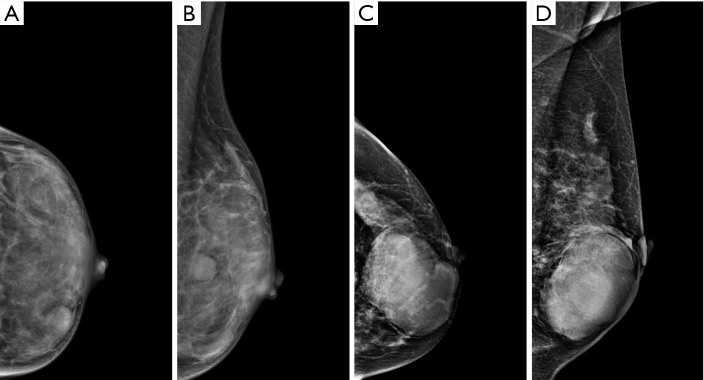

Background: Differentiation between breast phyllodes tumors (PTs) and fibroadenomas (FAs) remains a key clinical challenge, which is critical for formulating clinical treatment strategies. This study aimed to establish a fusion model based on mammography (MG) and magnetic resonance imaging (MRI) for the preoperative differentiation of PTs and FAs.

Results: A total of 147 patients with FAs and 138 patients with PTs were included in this study. Patient age, maximum diameter of mass, density on MG images, lobulation on MR images, and time-intensity curve (TIC) were independent factors contributing to the differential diagnosis. Finally, the fusion model showed satisfactory discrimination [area under the curve (AUC) 0.90, 95% confidence interval (CI): 0.86-0.94] and calibration. DCA indicated good clinical benefit, as indicated by most values being within threshold probabilities.

Conclusions: Breast MG and MRI findings help differentiate between FAs and PTs preoperatively. The multimodal fusion model was clinically efficacious and thus useful for accurate clinical diagnosis and treatment.